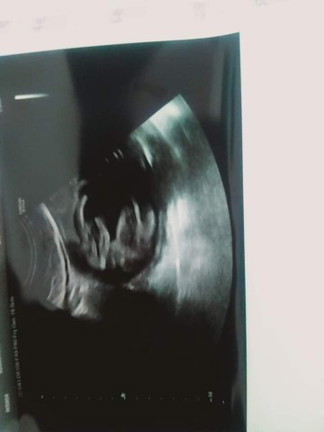

เเม่ๆว่าช/ญค่ะ คอมเม้นมาหน่อยค่ะ เเต่คุณหมอบอกผู้หญิงกลัวคลอดออกมาจะเป็นผู้ชาย หมอบอกไม่ชัวต้องรอลุ้นอีกทีในห้องคลอด

จริงๆภาพไม่ชัดเลยค่ะ ภาพสั่นนิดๆ แต่ไม่เห็นว่ามีจู๋นะคะ เรียบไปเลย อาจจะ ผญ ค่ะ